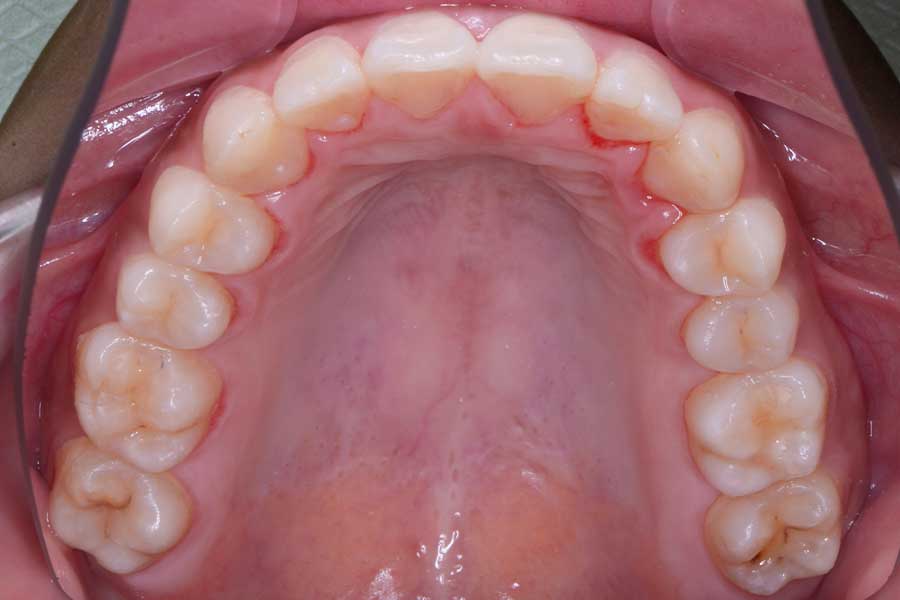

治療後

主訴 前歯の形と並びを良くしたい

治療内容 上下顎リンガル矯正(裏側矯正)